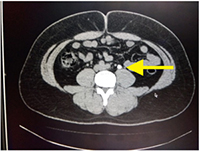

症例1:尿管結石

腎臓で作られた石が腎臓と膀胱を繋ぐ尿管という管に落ちて腹痛を伴う病気です。